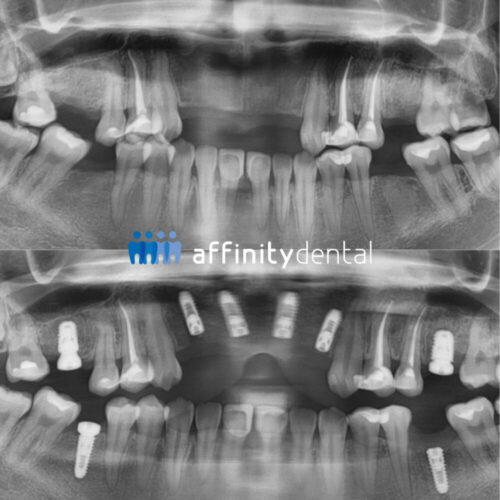

Before and after panoramic X-ray showing full mouth dental implants performed by Dr. Villanueva, Chief Implant Specialist at Affinity Dental Clinics Makati.

Panoramic X-rays before and after a full mouth dental implant surgery by Dr. Villanueva, Fellow of the Philippine College of Oral Implantologists and Chief Implant Specialist of Affinity Dental Clinics, performed at the Makati Center for Oral Surgery and Implant Dentistry.